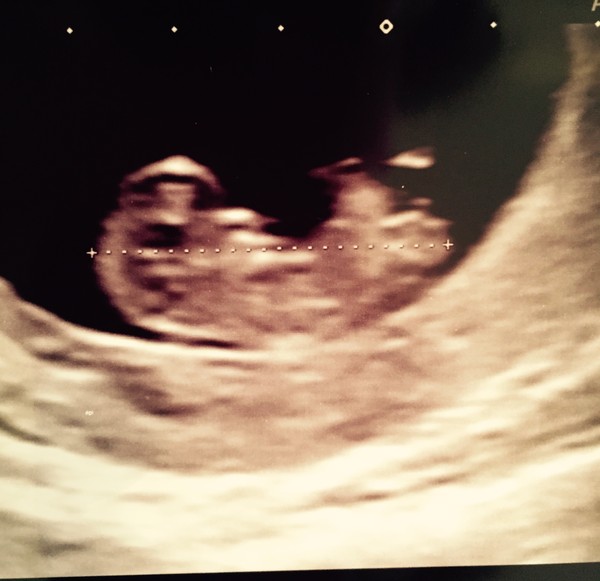

And talking of scan pics, here's my 10 weeks pic from the weekend ??

Just came off the app to have a look at your scan picture, how cute focusfocus!

Focusfocus tell us about the scan. It's my first pregnancy so all new. Did the have a problem finding the bean? Everything looks perfect in the pic such a relief for you. Mine is tomorrow evening.

Lovely scan focus! :)

Ah focus what a lovely picture Smile look at your little baby!

Lovely scan pic, Focus! Smile